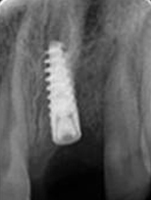

After 6 months

Placement of Bone Grafting

X-ray of Implant

X-ray of Implant + Abutment

X-ray of Implant +

Abutment+ Prosthesis